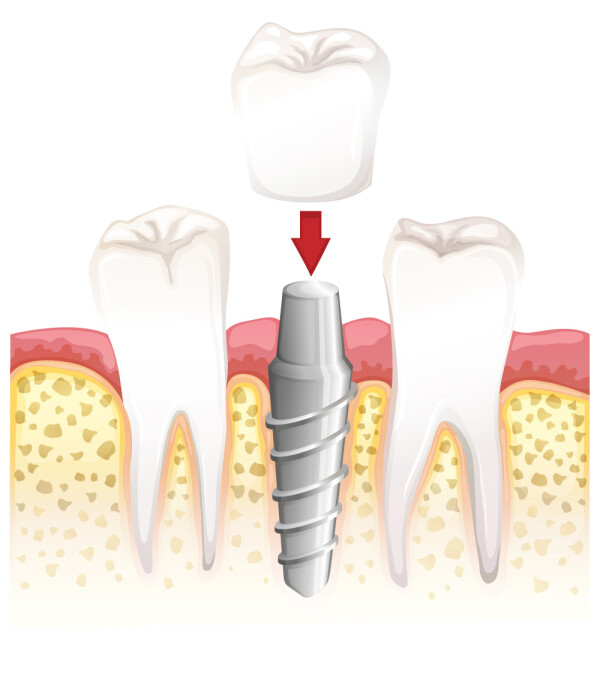

Voor ons is er dus reden genoeg om op onze website bij deze tandheelkundige specialisatie stil te staan. Implanteren is meestal een korte en voor de patiënt weinig belastende behandelmethode met uitstekende resultaten.

Hier kunt u de producten terugvinden die voor deze behandeling worden toegepast.